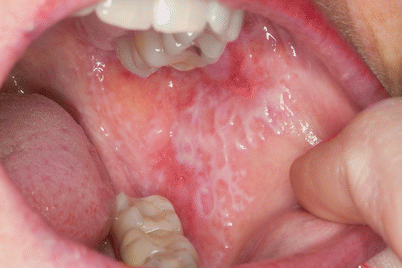

Multiple subtypes of OLP have been described: reticular, erosive, atrophic, papular, plaque, and bullous. Ulcerative OLP is the most common subtype reported in studies, likely due to symptomatology and severity of disease [26, 28]. However, clinical experience indicates that the reticular subtype is more common but patients are less likely to seek medical care due to its indolent and often asymptomatic nature. The lesions are often symmetrical and the buccal mucosa is the most common site of involvement (80–90 %) (Fig. 31.5) [25, 29–32]. Gingival involvement is uncommon, being the sole presentation in 8 % of cases, but remains the most common cause of desquamative gingivitis (75 % of cases) [33]. The classic lacy streaks (Wickham striae) are most commonly seen on the buccal mucosa. Koebnerogenic factors: smoking, dental caries and amalgams may exacerbate disease.

Fig. 31.5

Oral lichen Planus: Typical lace-like whitish, reticulated pattern (Wickham striae) on the buccal mucosa